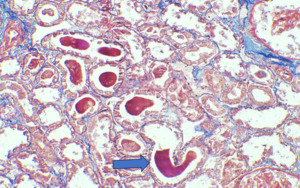

On Light microscopy, The H &E-stained sections of renal biopsy showed features of acute tubular epithelial cell injury with swollen, attenuated lining epithelium. Numerous tubules showed pink to red brown casts in the lumen which were grainy to globular and ropy at places. (Figure 1). The casts appeared weakly PAS positive (Figure 2) and fuchsinophilic on MT stain (Figure 3). On IHC, these casts gave positive staining for myoglobin (Figure 4).

According to one study, other associated finding may be of arterial sclerosis and deposition of calcium oxalate.3 Myoglobin casts are usually appeared eosinophilic to brown granular in H&E stain, are weakly PAS positive and fuchsinophilic in MT stain. Differential diagnosis of Myoglobin casts includes other pigment casts like haemoglobin casts and bile casts.5,11–13